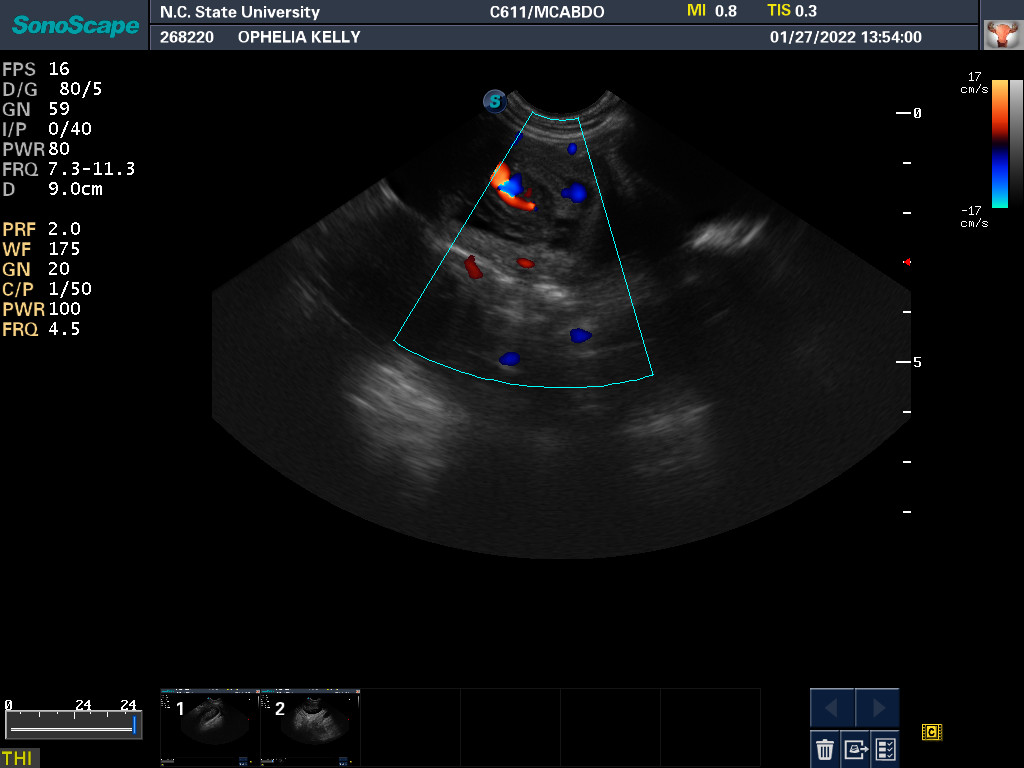

22 Feb

This morning I took Ophelia to NC State. Yesterday Ophelia's progesterone was around 8 ng/mL. Today it is around 4 ng/mL. So no puppies today. What my repro vets want to see is around 2 ng/mL. They also ultrasounded the puppies looking for GI movement and checking their heartbeats. On the way home I stopped at a grocery store and stocked up on cottage cheese and plain whole yogurt, which will be necessary when the puppies come.